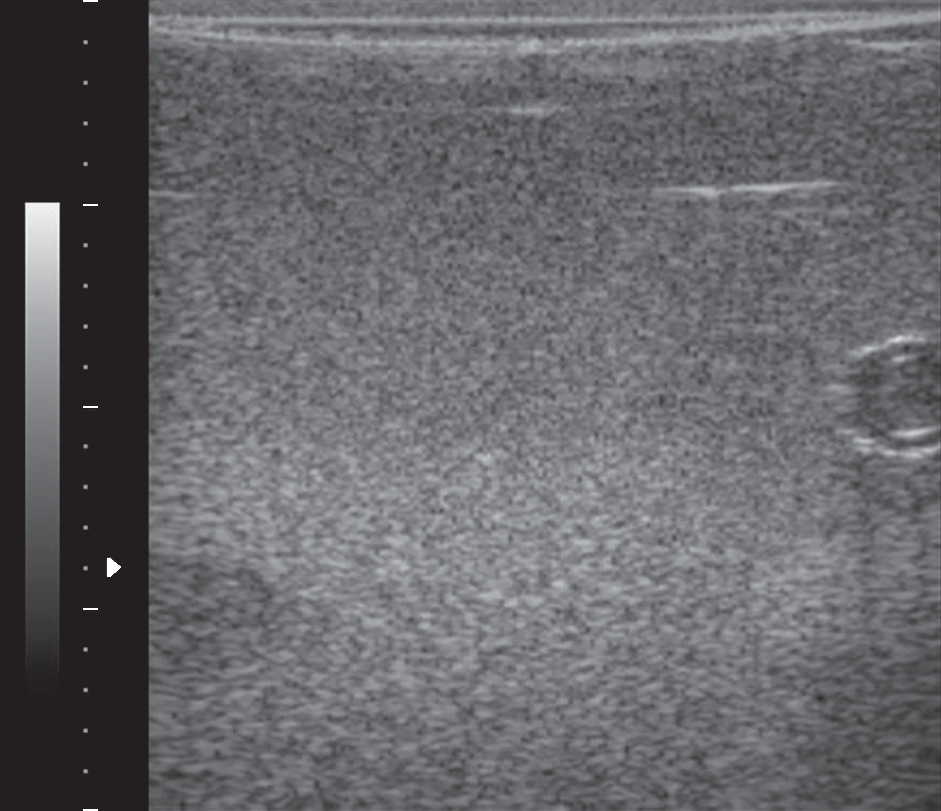

В работе рассматривается принципиально новый подход к решению задачи определения размеров структурных образований при ультразвуковой диагностике, в основе которого лежит теоретически обоснованная возможность оценивания размеров неоднородностей исследуемой среды посредством анализа статистических характеристик рассеянного на этих неоднородностях ультразвукового сигнала. Эта возможность обусловлена тем, что статистическое распределение данных, формирующих ультразвуковое изображение, варьируется от распределения Рэлея до распределения Райса в зависимости от соотношения между размером области когерентности рассеянного сигнала и шириной луча. Работа направлена на развитие нового метода статистического анализа данных, который позволит эффективно выявлять значительную когерентную составляющую в эхо-сигнале и тем самым будет использоваться как математический инструмент оценивания размера неоднородностей среды при ультразвуковой визуализации. Такой подход к анализу ультразвуковых изображений обеспечит возможность количественного оценивания структурных образований и тем самым – существенное повышение информативности ультразвуковой диагностики и возможность выявления патологий на ранней стадии их образования, открывая перспективы повышения эффективности лечения.